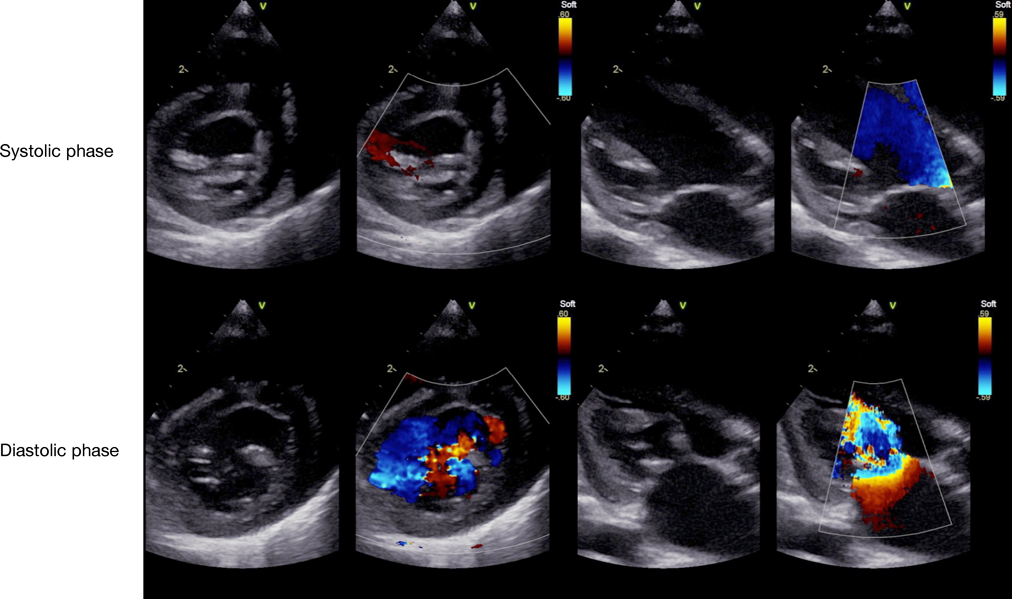

術後経過

術後11日の心臓超音波検査では,MRは消失し,Vmax 1.5 m/sであった(Fig. 6).術後3年2か月時,MRの再発はなく,自己心膜を含めた後尖の可動性は低下しているものの,自己心膜の肥厚は軽度で,石灰化は認めていない.Vmax 1.6 m/sと進行は認めていない(Fig. 7).

Pediatric Cardiology and Cardiac Surgery 35(1): 52-58 (2019)

Fig. 6 Postoperative echocardiogram (11 days) of case 2

Mitral valve regurgitation disappears postoperatively.

Fig. 7 Postoperative echocardiogram (3 years and 2 months) of case 2

The augmented autologous pericardium is mildly thickened and its movement is decreased. Mitral valve regurgitation is still none.